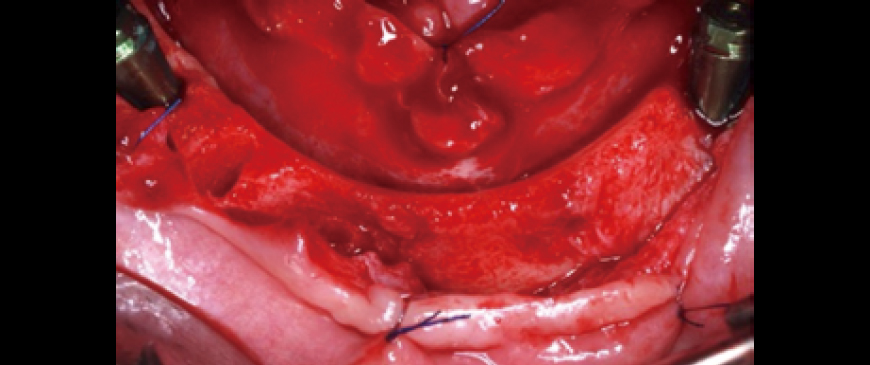

Fig 6

The three fixtures have been successfully placed. The BD Cuff implant in the second premolar extraction socket effectively covers the socket defect with its machined cuff. Additionally, the BD Cuff in the first molar region ensures that even if the thin buccal cortical bone undergoes resorption, the threads will remain covered, allowing for healthy and long-term functional stability.

Fig 7

A small amount of allograft was placed in the second premolar extraction socket defect, while the first molar region was left untreated and simply sutured. If the patient's gingival biotype had been thin, an additional material like Ossix Volumax would have been used.

Fig 8

Postoperative panoramic and CBCT radiographs revealed minimal buccal bone thickness around the first molar implant, with the machined cuff of the BD Cuff occupying this space (indicated between the two arrows).